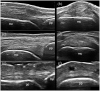

Bone erosions are the hallmark of structural damage in rheumatoid arthritis (RA). Among imaging techniques, ultrasonography (US) has emerged as an accurate, reliable, repeatable, low-cost and non-invasive imaging modality to detect erosive changes in RA. However, small interruptions of the cortical bone detectable by last generation US equipment do not necessarily represent bone erosions. According to the available data, in addition to cortical bone interruption itself, only a few morphological US findings have been proposed to define RA bone erosions. However, other additional features may be considered to facilitate the interpretation of US cortical bone interruptions in RA. These could be summarised using the following four domains: size, site, shape and scenery. This hypothesis article provides a critical literature review of US features characteristic of RA bone erosions and pictorial evidence supporting the potential role of a morphological analysis in the US identification of bone erosions in RA patients.

Plain language summary: The ultrasonographic morphology of cortical interruptions is helpful for the identification of bone erosions in rheumatoid arthritis: the "four Ss" approach Bone erosions are characteristic features of rheumatoid arthritis. They are associated with a more aggressive disease and with irreversible physical disability. In recent years, ultrasonography has emerged as an accurate and reliable technique for the detection of bone erosions, that appear as interruptions of the cortical bone with variable size. However, cortical bone interruptions do not necessarily represent bone erosions. Since bone erosions represent the earliest evidence of the destructive behaviour of RA, their identification is crucial.Besides the cortical interruption itself, only a few morphological ultrasonographic features were proposed to characterise bone erosions in rheumatoid arthritis.We believe that a morphological approach, including size, site, shape and scenery, may be considered to facilitate the interpretation of ultrasonographic cortical bone interruptions in rheumatoid arthritis.In this hypothesis article we carried out a critical review of the scientific literature and provided extensive pictorial evidence of the ultrasonographic spectrum of cortical interruptions supporting the potential role of considering the "four Ss" for the ultrasonographic identification of bone erosions in rheumatoid arthritis.